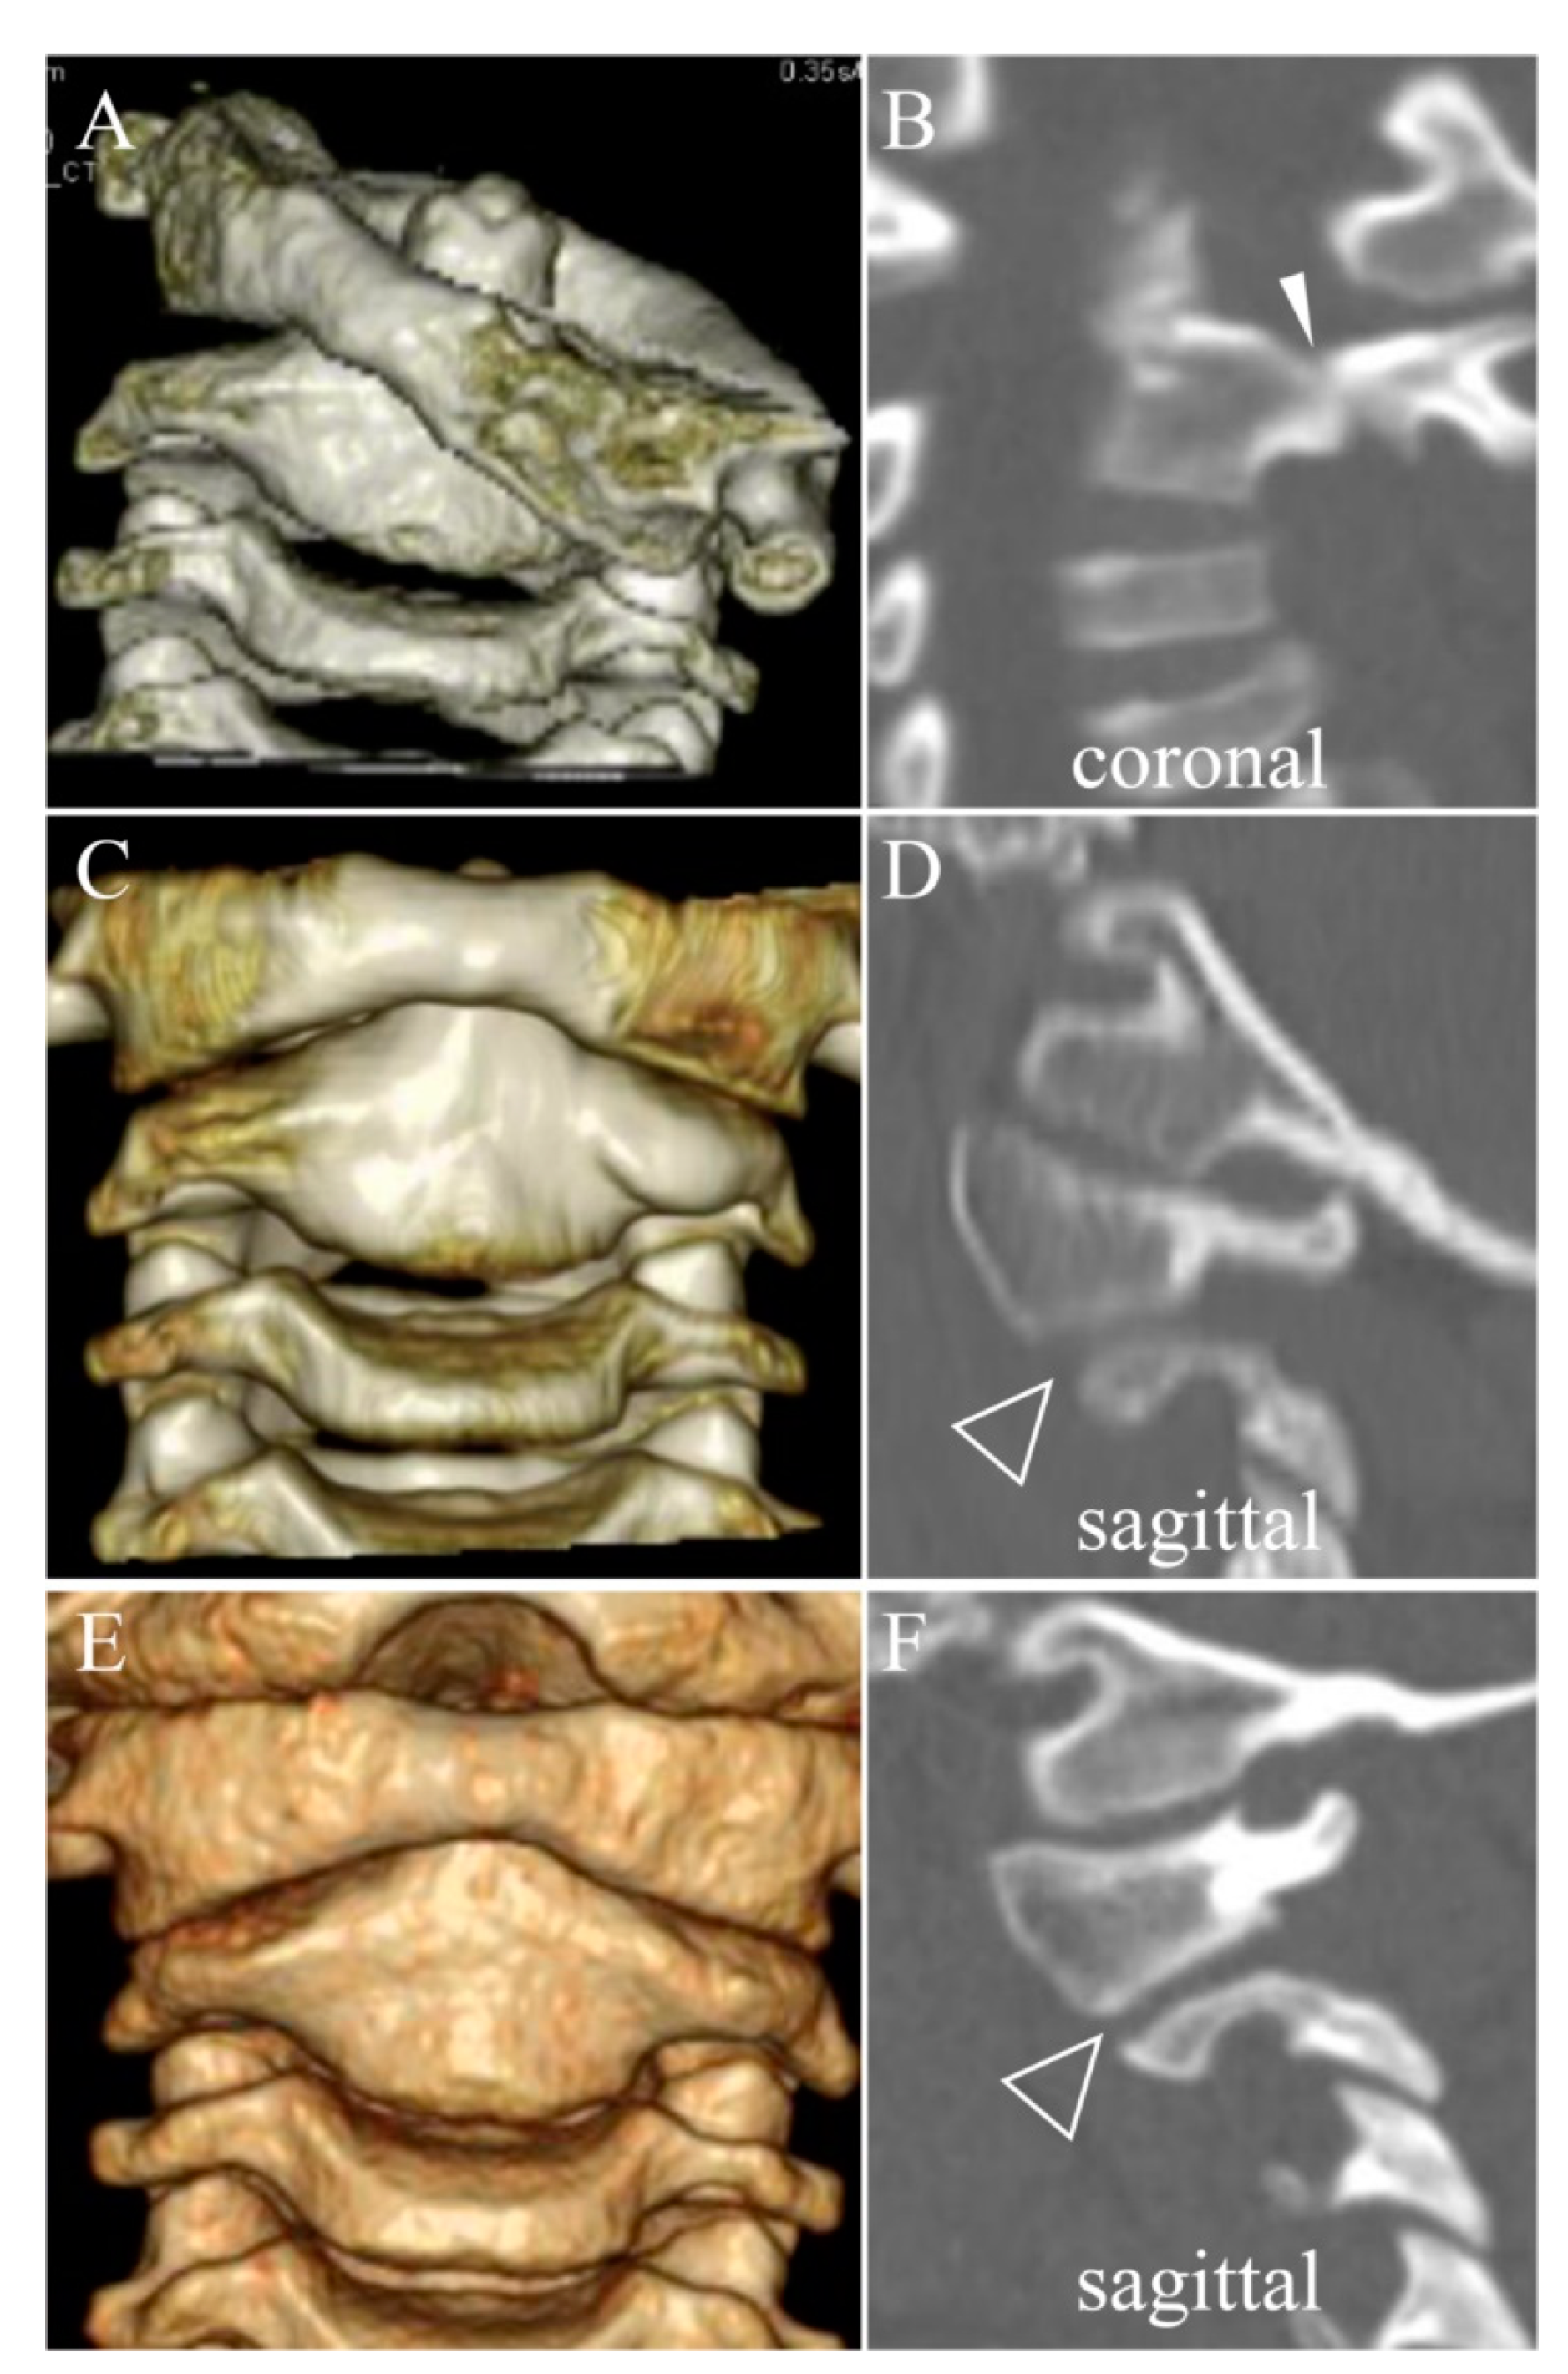

3.3. Direct Osseous Contact of the Facet Joint before and during Halo Fixation

4.1. Spontaneous Osseous Fusion after Halo Traction/Fixation

| SOF | Spontaneous Osseous Fusion of affected vertebrae which is confirmed after remodeling therapy for chronic AARF |

| DOC | Direct Osseous Contact of facet joints which is defined as disappearance of facet joint space between the adjacent vertebrae on sagittal or coronal CT images. |